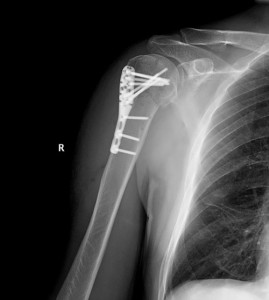

Оперативное лечение травм хирургической шейки основывается на проведении открытой репозиции и фиксации костных отломков одним из способов. Существует уникальный фиксатор, который имеет термомеханическую память. Он изготовлен из специальных сплавов и имеет изогнутые конструкции. Они, кроме удержания отломков, сближают их. В костных фрагментах делают отверстия.

Фиксатор охлаждают и придают его элементам форму, которую удобно внедрять в сделанные отверстия. В тканях фиксатор нагревается до 37 градусов, поэтому металл принимает прежнюю форму. Это позволяет скреплять и компенсировать отломки. Такой остеосинтез настолько стабилен, что можно обойтись без внешней иммобилизации.

В других случаях после проведения операции нужно накладывать торакобрахиальную повязку из гипса. Однако ее применяют для лечения травм хирургической шейки у молодых людей. У людей старшего возраста фиксацию производят с помощью повязки-змейки или клиновидной подушки во впадине под мышкой. Металлические фиксаторы убирают через несколько месяцев после проведения операции, однако, перед этим нужно убедиться в том, что произошло сращение отломков.